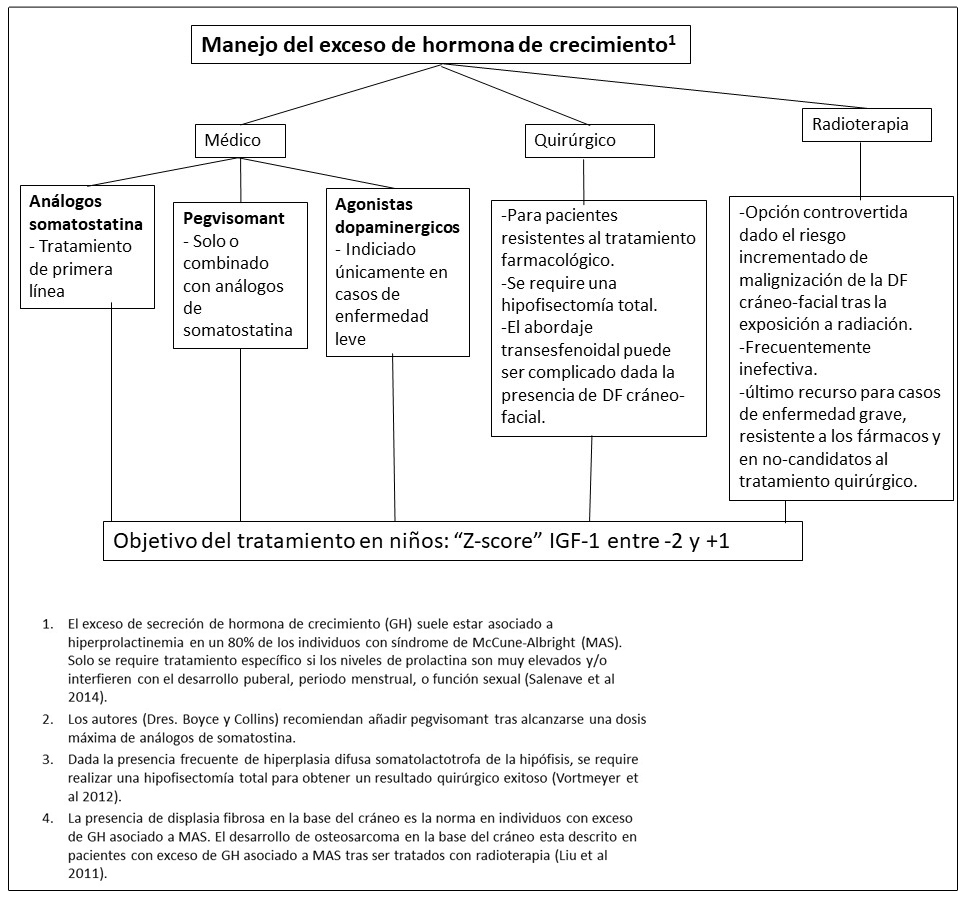

- Boyce et al 2013, Salenave et al 2014.

- El tratamiento con radiación puede ser efectivo en casos refractarios, pero se ha asociado a la transformación maligna de la DF cráneo-facial (Hansen &Moffat 2003, Liu et al 2011).

- La cirugía puede ser técnicamente compleja o imposibilitada por la presencia de DF cráneo-facial. Asimismo, dada la infiltración difusa de las células somatotrofas (células pituitarias productoras de GH), los individuos afectos requieren una hipofisectomía total si se intervienen mediante cirugía. Esto resulta en un hipopituitarismo total (Vortmeyer et al 2012).

- Esta clase de medicamentos puede tener un efecto en el tratamiento de exceso de GH en aquellos individuos con elevaciones leves de GH e IGF-1, con o sin hiperprolactinemia asociada (Katznelson et al 2014).

Figura 15. Recomendaciones para el manejo del exceso de hormona de crecimiento en pacientes con Displasia Fibrosa/Síndrome de McCune-Albright